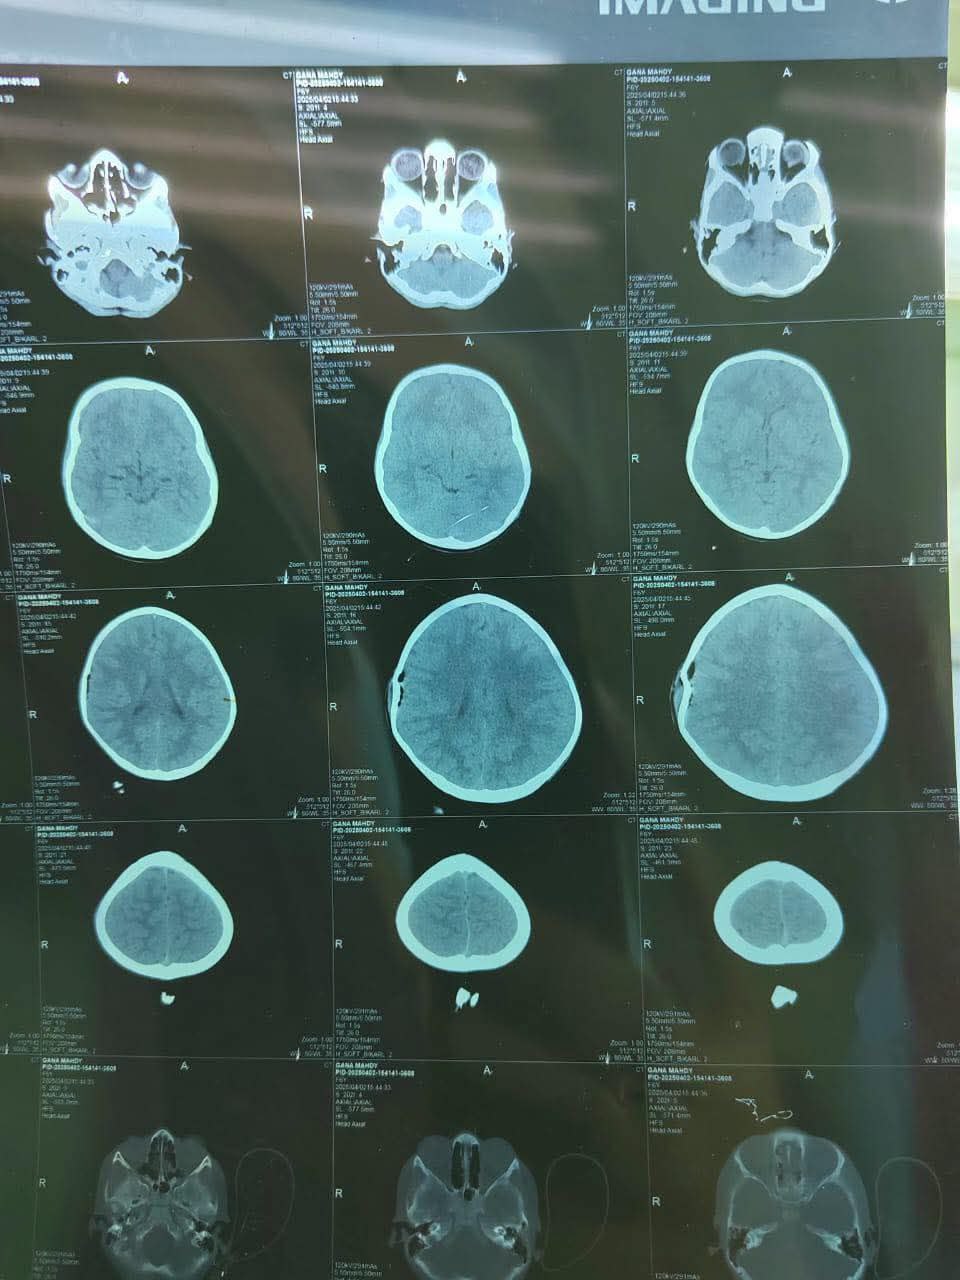

ومن جانبه أوضح” الدكتور “مصطفى محمد الحيدري” : الطبيب الاختصاص الخافر في جراحة الجملة العصبية ، أن الإصابة أدت إلى كسور متعددة ومعقدة منخسفة في الجمجمة ، وضغط على الدماغ ، إضافة إلى نزف فوق الأم الجافية وتمزق في الشرايين السحائية ، وهي إصابات تُعدّ من الحالات الحرجة التي تهدد حياة المريض .